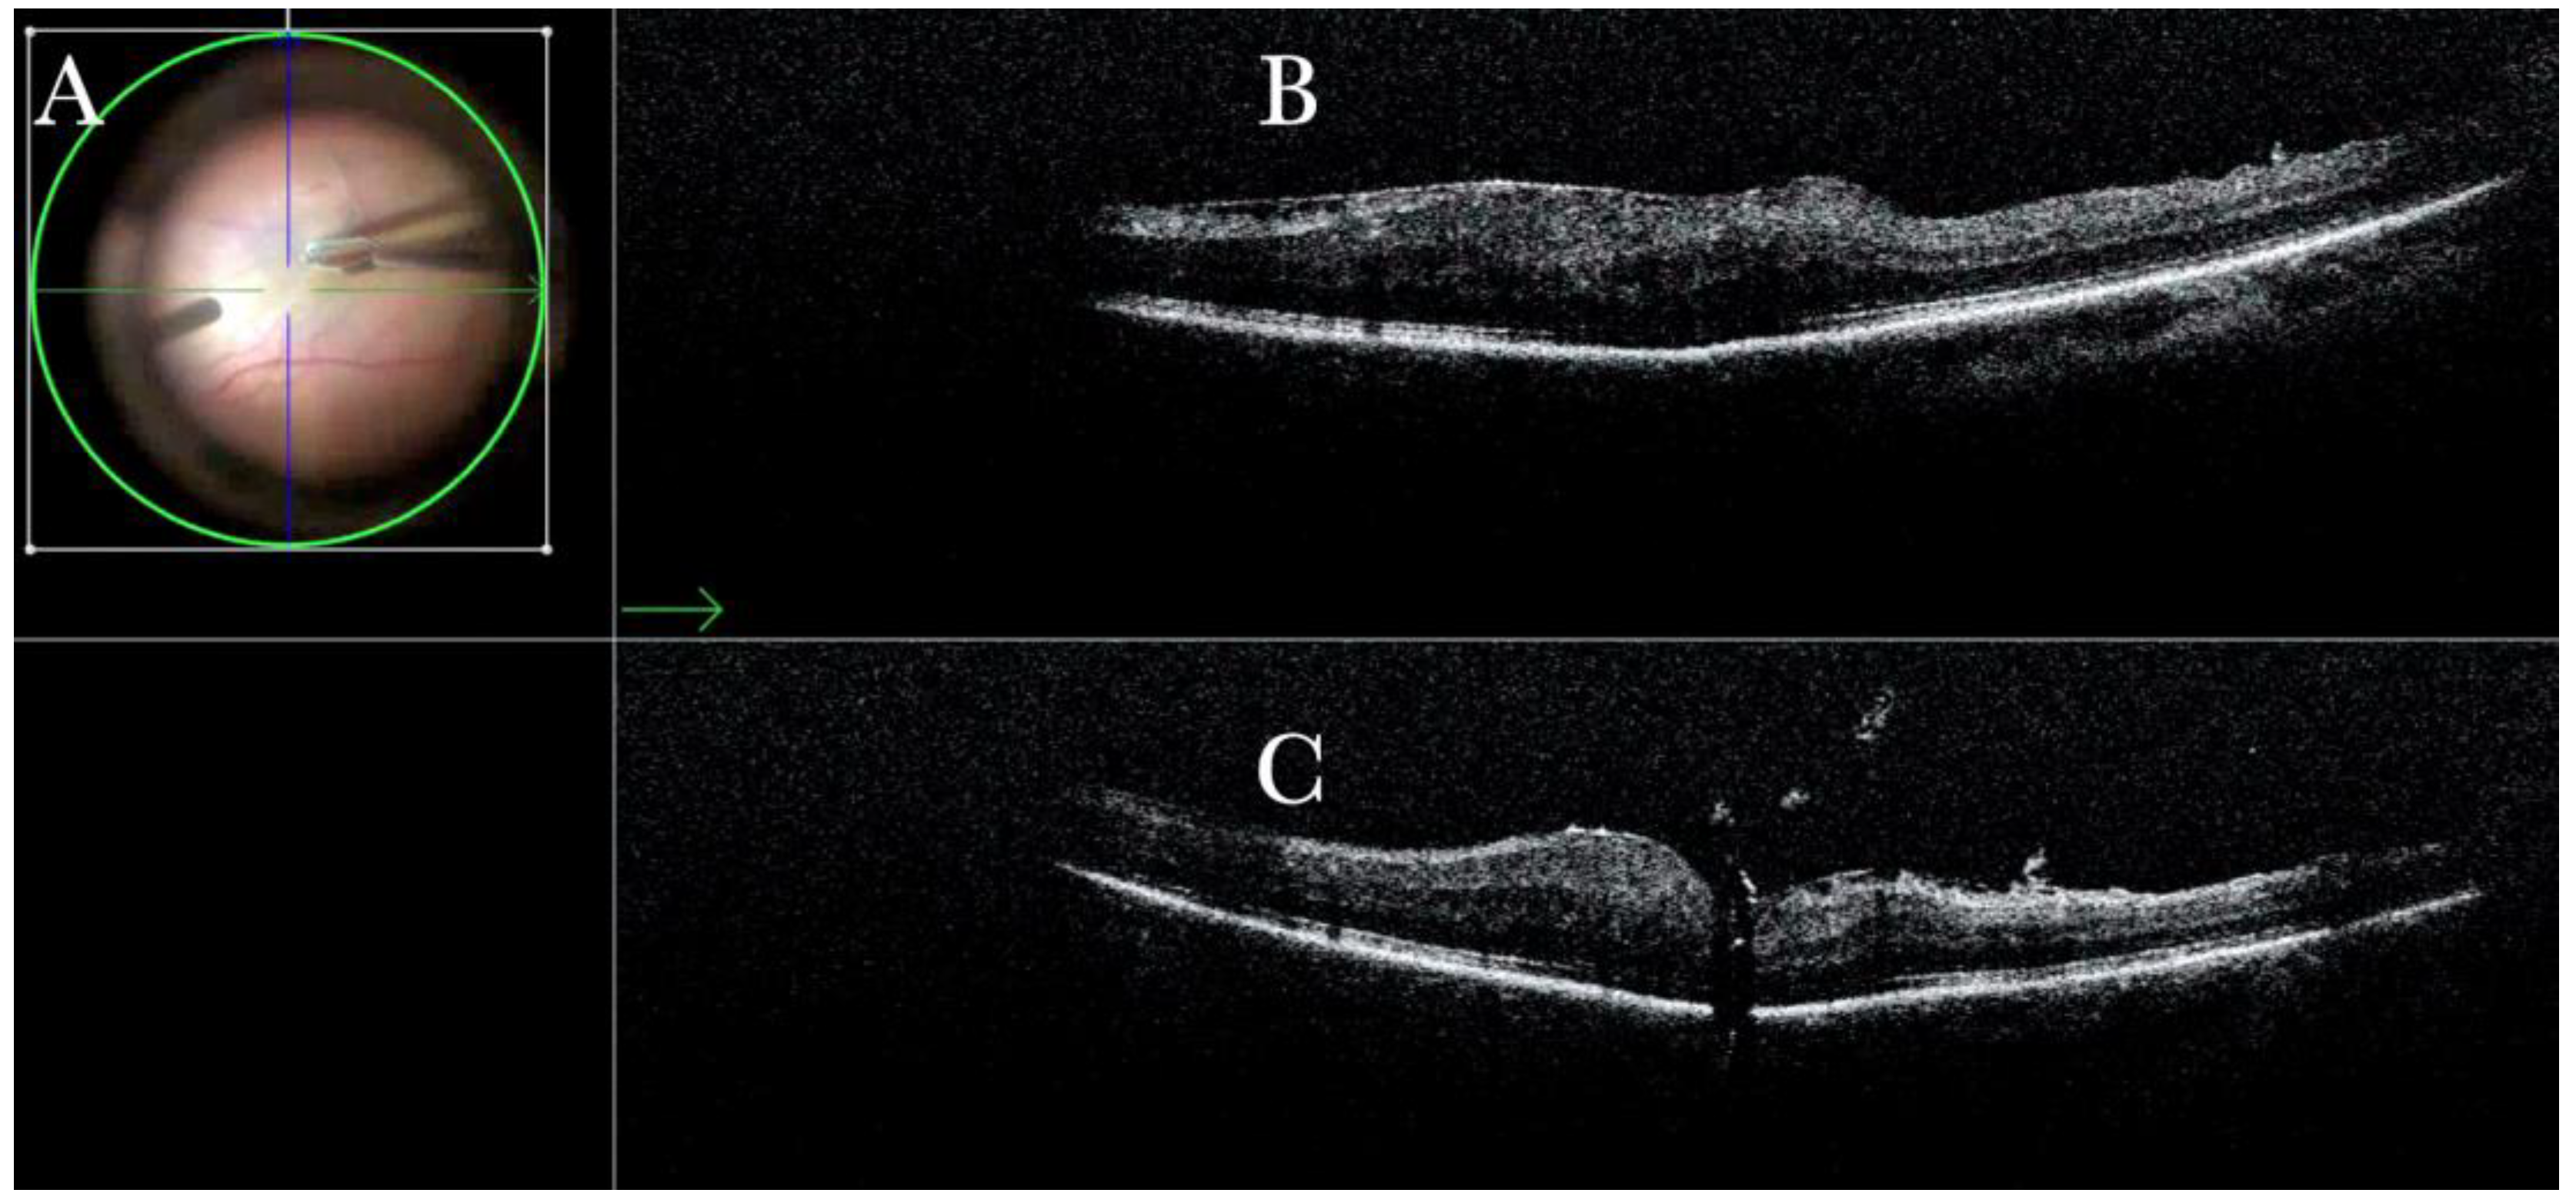

Figure 19.

(A) Microscope view of a case of retinal detachment with proliferative vitreoretinopathy (PVR). The retina is stained with Doubledyne blue. However, it is not clear where the PVR membranes are located. (The green box indicates the field-of-view of the OCT scan, the green and blue lines within the green box show the vertical and horizontal scan planes). (B) The horizontal (green arrow) intraoperative optical coherence tomography (i-OCT) scan shows an area of retina thickening and wrinkling, indicating the presence of an epiretinal membrane (ERM). (C) The vertical i-OCT scan (thin blue arrow) shows an area of retina thickening and wrinkling, indicating the presence of an ERM (thick blue arrow).

Figure 20.

(A) Microscope view of the same case of retinal detachment with proliferative vitreoretinopathy (PVR). The retinotomy is analyzed. The surgeon needed to decide whether to peel the epiretinal membrane (ERM) at the edge of the retinotomy and elevate the retinotomy to lower the traction. It is not clear through the microscope how to proceed. (The green box indicates the field-of-view of the OCT scan, the green and blue lines within the green box show the vertical and horizontal scan planes). (B) The horizontal (green arrow) intraoperative optical coherence tomography (i-OCT) scan shows the retinotomy, indicating the presence of an ERM and squared edges. (C) The vertical (blue arrow) i-OCT scan shows the same area after peeling the ERM, elevating, and reattaching the retinotomy. The retinotomy is now flat and relaxed.